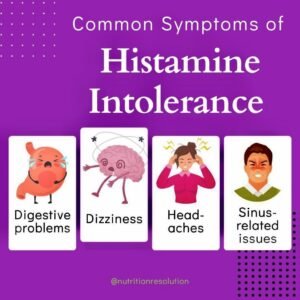

Anti-Histamine

Read more -